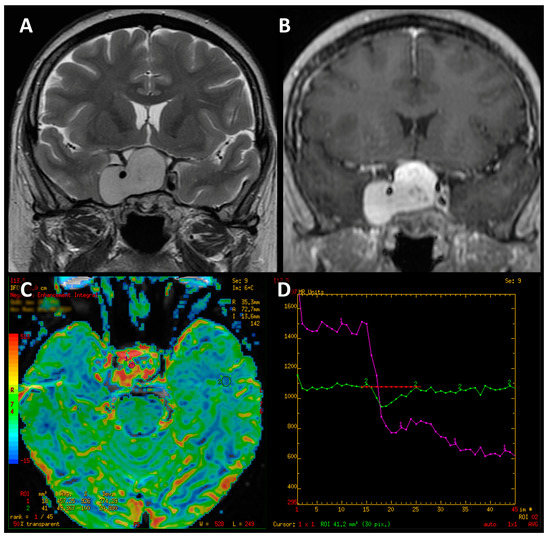

- Mean perfusion parameters for the whole tumor (labeled as rCBV’1)—the arithmetic mean of the perfusion values collected by outlining the tumor with ROIs on each axial slice (Figure 4A).

- Mean of maximum perfusion parameters (labeled as rCBV’2)—the arithmetic mean of the maximum perfusion values collected by outlining the regions with the highest values with circular ROIs (about 30–60 mm2) on each axial slice of the tumor (Figure 4B).

- Maximum perfusion values (labeled as rCBV’3)—the maximum values collected from the whole tumor with a circular ROI (about 30 mm2–60 mm2) (Figure 4B).